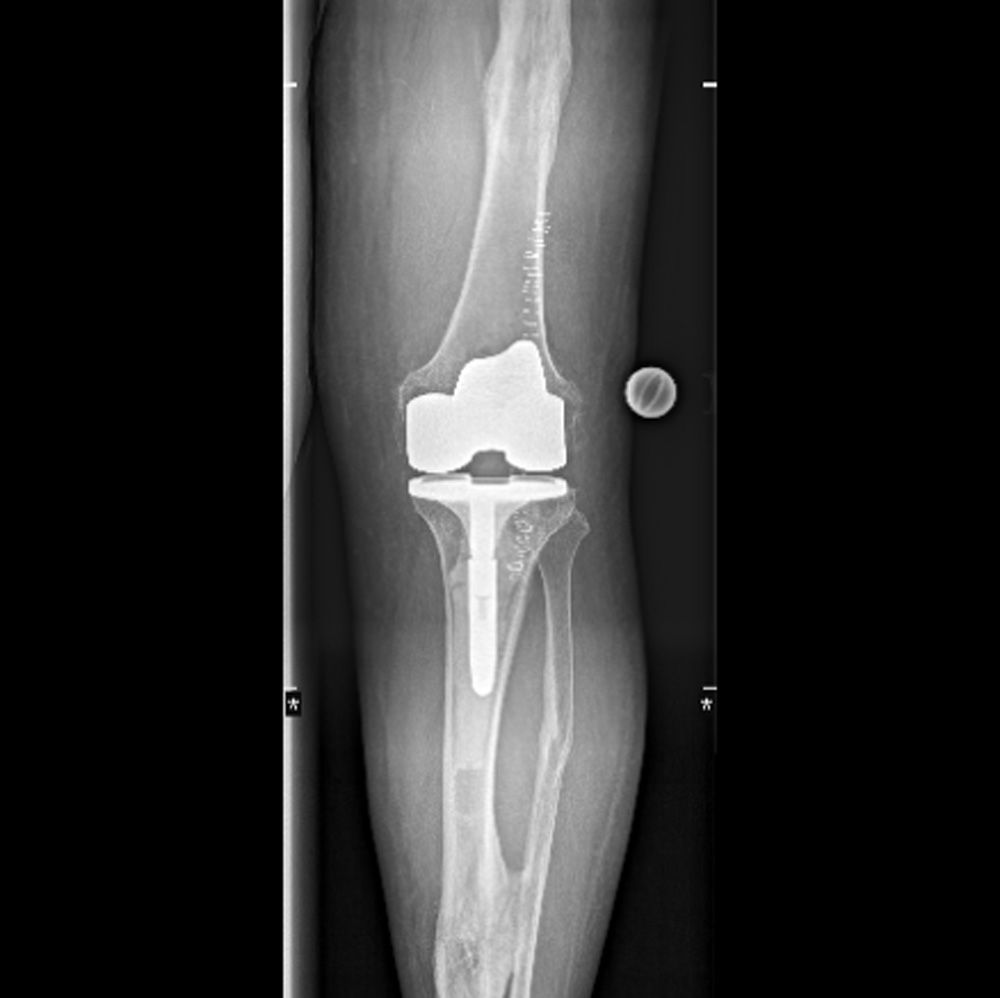

Röntgenaufnahme eines Kniegelenks mit implantierter Knieendoprothese in Frontalansicht.